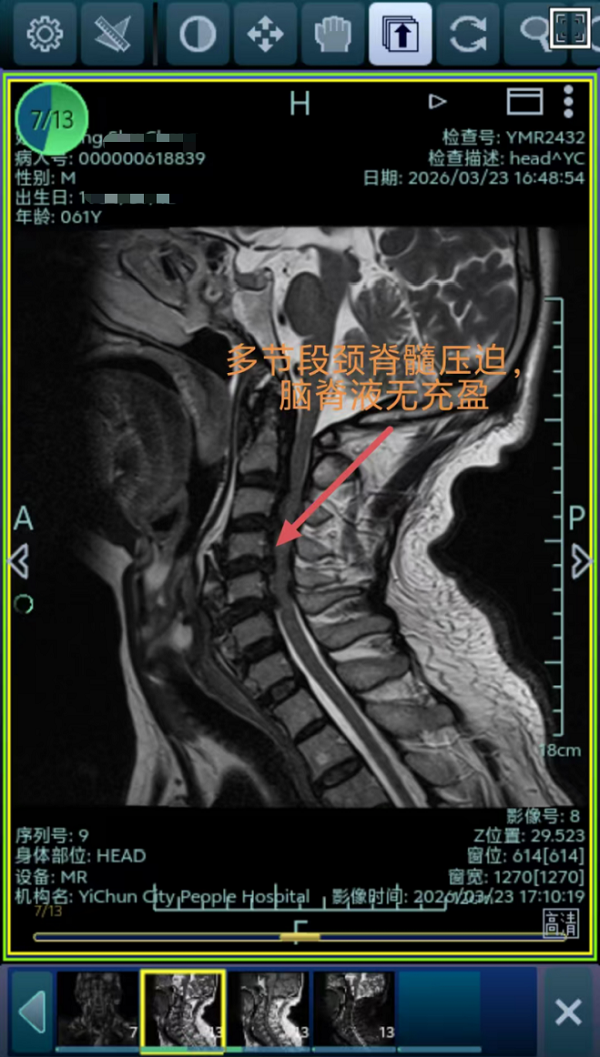

2.上颈椎高风险手术(四级手术):患者因颈脊髓损伤导致高位截瘫入院,病情危急。更为棘手的是,患者同时合并糖尿病、高血压、脑梗等多种基础疾病,身体状况复杂,手术及麻醉风险极高。上颈椎(C1-C3区域)手术毗邻延髓、椎动脉等生命中枢,解剖结构复杂,操作空间狭小,向来被视为脊柱外科手术的“禁区”。

面对这一严峻挑战,脊柱外科团队启动多学科协作机制。制定了周密的围手术期管理方案与应急预案。术中在麻醉科的精准护航下,丁晔副主任医师为患者实施了堪称“刀尖上舞蹈”的颈椎后路C1后弓切除+C2穹顶减压+C3-C6椎板扩大减压成型术。该手术技术要求极高。术中可见脊髓减压充分,手术过程顺利。术后患者躯干及肢体的感觉功能已开始逐步恢复,为后续康复奠定了坚实基础。